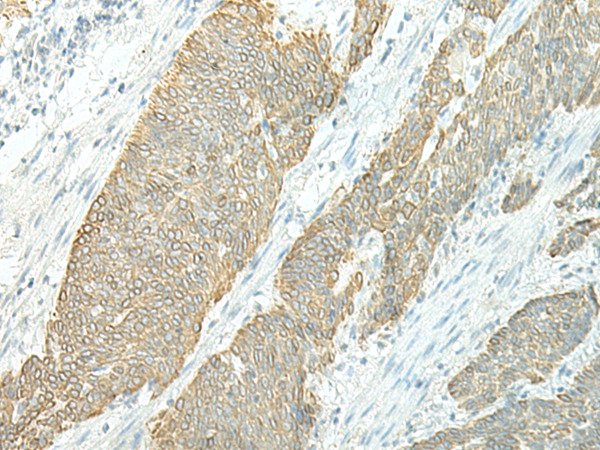

IHC positive control: |

Human esophagus cancer and Human thyroid cancer |